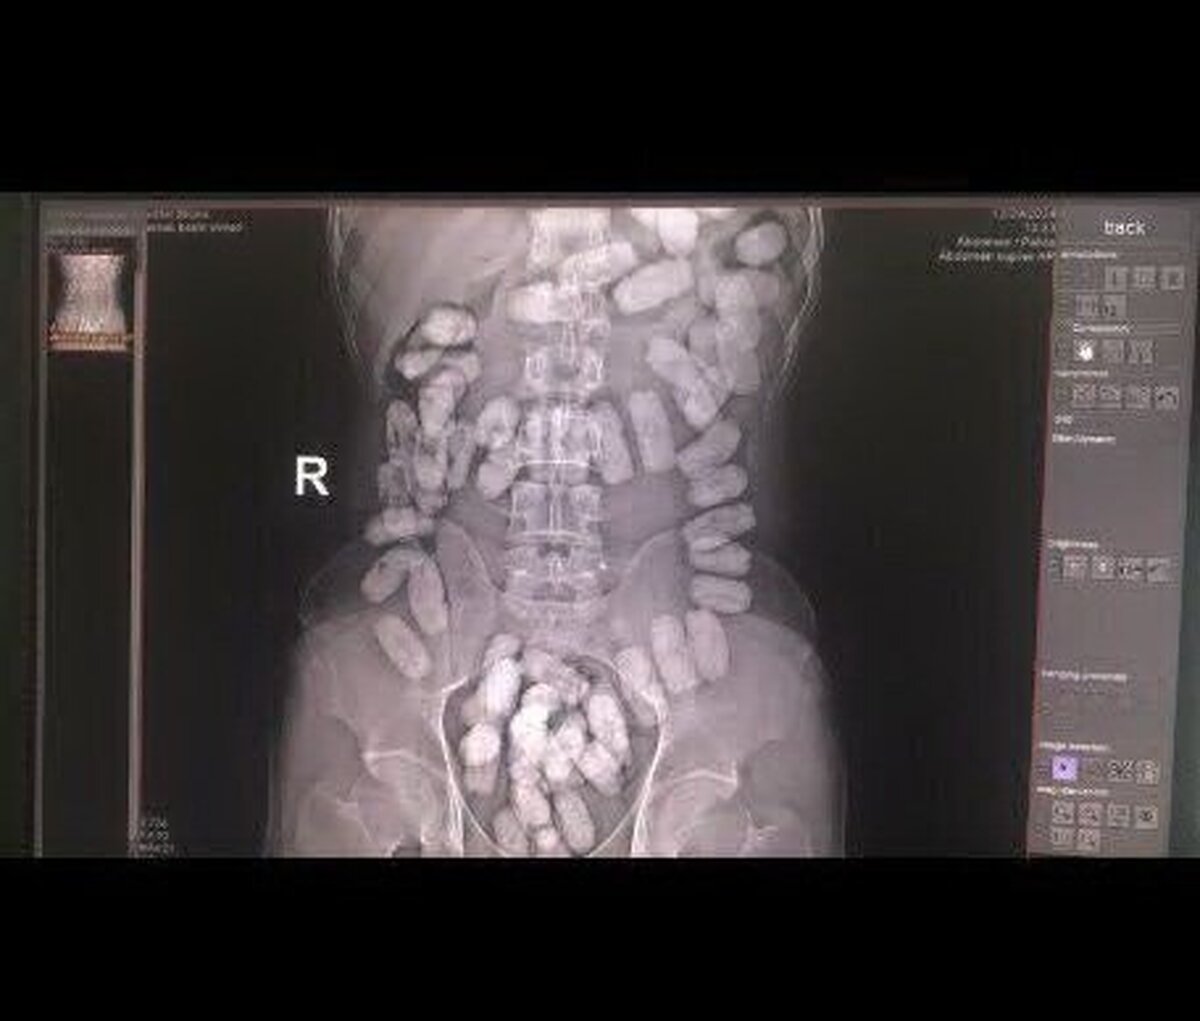

کشف ۵۵ بسته هروئین از معده یک مسافر

جانشین فرمانده مرزبانی خراسان رضوی گفت: ۵۵ بسته مواد مخدر آب‌بندی شده به وزن ۵۵۰ گرم از نوع هرویین پودری که در معده جاسازی شده بود، از یک تبعه خارجی در هنگ مرزی تایباد کشف شد.

وی بیان کرد: این فرد ۵۵ بسته هروئین از طریق بلعیدن به همراه داشت که متهم دستگیر و به همراه مواد کشف شده تحویل مراجع قضایی شد.